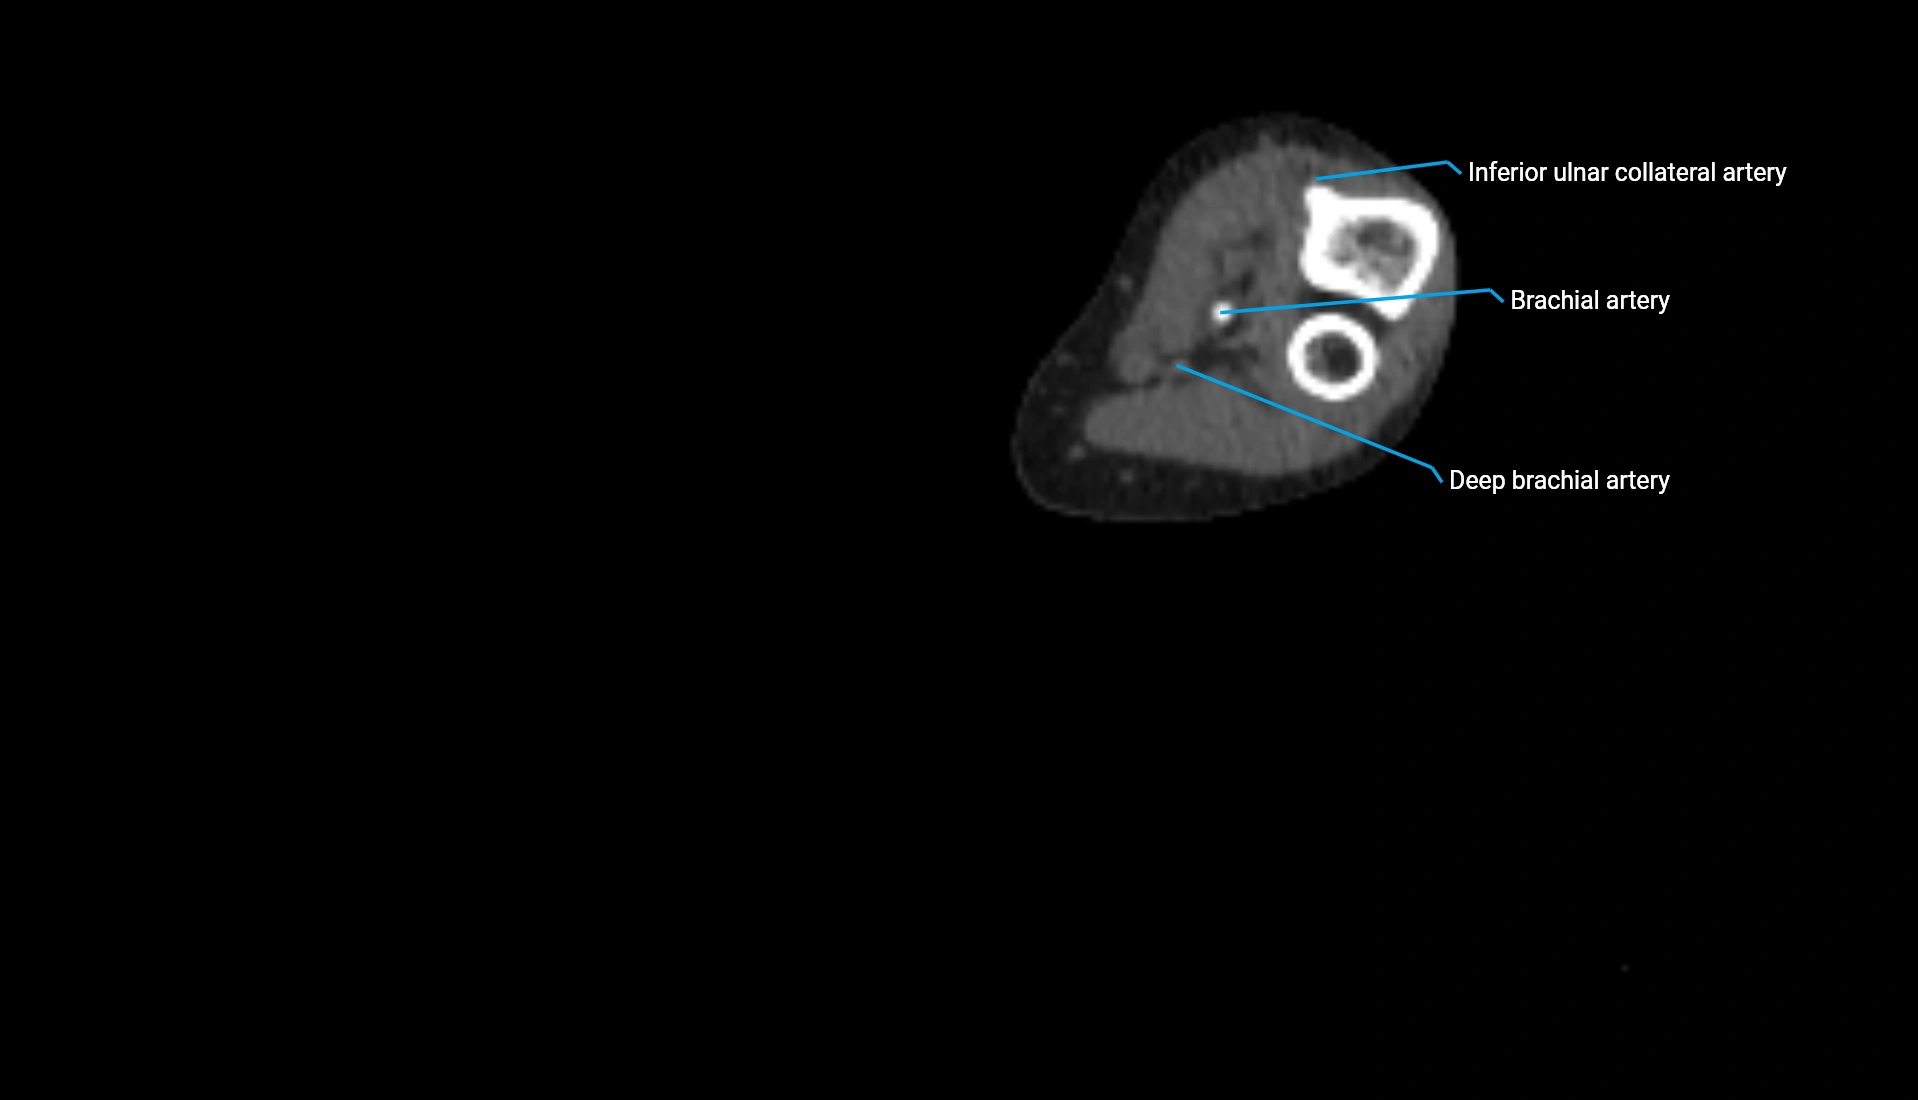

CT Appearance

Non-Contrast CT:

• Cortex: High-density, sharply defined

• Subchondral bone: Dense cancellous matrix

• Articular surface: Smooth concave contour articulating with the capitellum

• Excellent for evaluating bone integrity, alignment, and subtle fractures